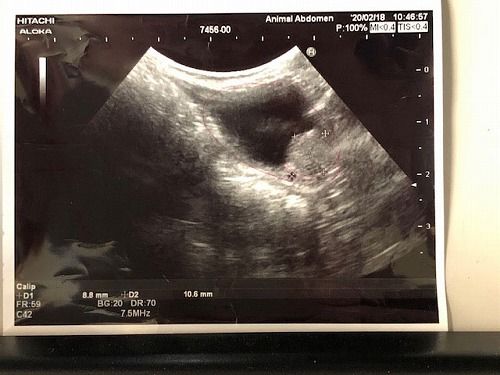

一番最初のレントゲン写真(当店に来る前)

この後「Pet水素」とアガリクス入りフード「AGARx」を使用開始

3週間後